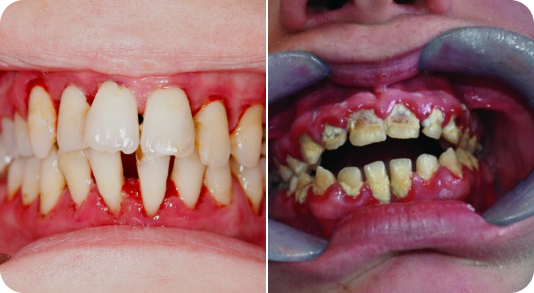

Gums can be treated for diseases leading to tissue infection, bone loss and loose teeth leading to gum disease that can occur when you do not take proper care of your oral health.

Using digital, advanced software, our dental experts will come up with a scientific The surgery can help treat the infected part of the gums by extracting the bacterial formation from under the tissue and sewing it back. This slowly reduces inflammation and prevents further gum disease, improving overall gum health and aesthetics of your facial structure.plan by predicting the result by analysing the tooth movements and deducing the invisible aligners before and after positions.

Take control of your gum health with advanced treatments! Gum surgeries offer effective solutions for gum problems that may not be resolved through non-surgical methods. From gum grafting to periodontal flap surgery, our skilled team will restore your gum health and help you achieve a healthier, more confident smile.